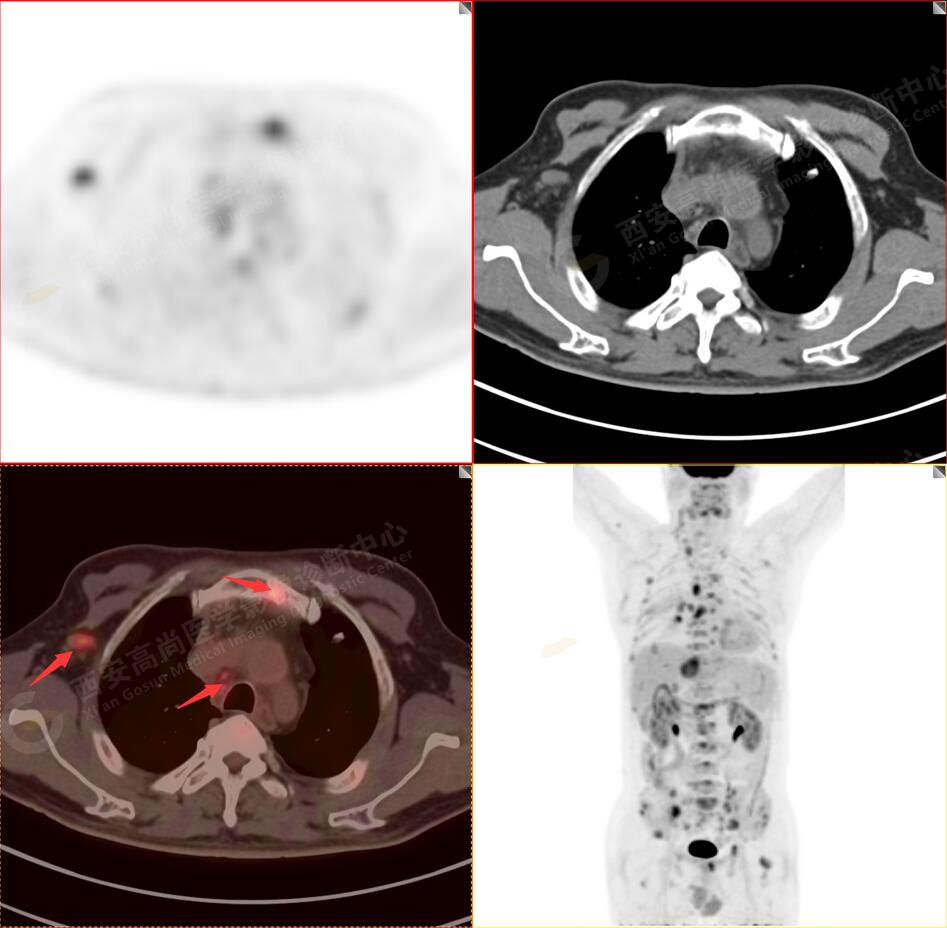

2.以下為全身多發(fā)轉移灶

3.右側頸部(Ⅱ-Ⅴ區(qū))、右側腋窩區(qū)、右側肺門及縱隔(1R、1L、2、4、6、7組)、肝門區(qū)多發(fā)腫大淋巴結,呈不同程度異常增高,均考慮為淋巴結轉移。

5.右側肱骨上段、左側肩胛骨、右側鎖骨胸骨端、胸骨、雙側多發(fā)肋骨、脊柱多發(fā)椎體及附件、雙側髂骨、雙側髖臼、雙側恥骨、雙側肱骨上段多發(fā)成骨性病變,呈不同程度FDG代謝異常增高,考慮為多發(fā)骨轉移瘤。

以上病變符合:T4N3M1c,ⅣB期(UICC/AJCC,2018年第8版肺癌TNM分期)。